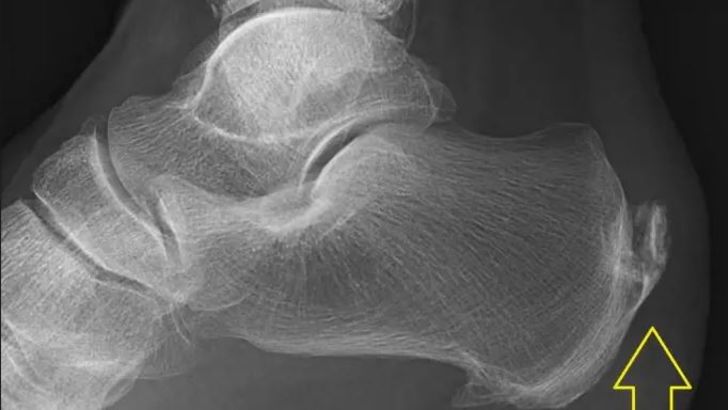

בצילום או בבדיקת אולטרה סאונד ניתן יהיה לראות בליטה בעצם העקב שלא אמורה להיות שם, ונראית כמו קוץ גדול. עם זאת, לא כל כאב יהיה מלווה בהוכחה בצילום. למעשה, לעתים יש כאב ובהדמיה לא נראה דבר.

4. בעוד שבעבר סברו שמקור הבעיה הוא בכף הרגל, היום יודעים שאין זה כך. הבליטה בכף הרגל לא גדלה ביום אחד ובוודאי לא ביום תחילת הכאב. הבליטה נמצאת שם כבר זמן רב.

יש להדגיש שלא בכל מקרה נראה בליטה בעצם בצילום, ולא תמיד התסמינים יהיו דומים. למעשה, אצל חלקנו יורגש כאב רק בשעות הבוקר, בעוד שאצל אחרים רק בזמן ריצה. עם זאת, עצמת הכאב תהיה שווה. כמו כן, במרבית המקרים הסיבה לכאב נעוצה באזור אחר בגוף, אך באה לידי ביטוי בכף הרגל, וזו הסיבה שלטיפול כפי שניתן עד לאחרונה הייתה הצלחה מוגבלת מאוד.